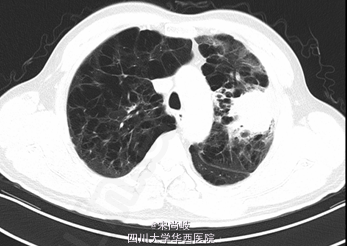

胸廓桶状,双肺呼吸音过清。胸部CT提示双肺慢支炎肺气肿表现,左肺上叶见4.9*4.0CM软组织肿块。

诊断为:左上肺包块。全麻下行剖胸探查+左肺上叶肿物取活检术,术中见胸内淡黄色积液50ml, 轻度粘连,胸膜有种植; 肿块位于肺门部及上下肺叶,约8*7*7cm大小,有脏层胸膜皱缩、有侵犯壁层胸膜;肿瘤距隆突<2cm,侵及纵隔胸膜,心包;淋巴结肿大及侵犯情况:7组,10组,11组淋巴结肿大,质硬,与周围组织紧密粘连;术中冰冻果:(左上肺肿物)倾向非小细胞型肺癌,术中特殊情况:左上肺肿物侵入左下肺及左肺门部,质硬,活动度差,周围淋巴结肿大,质硬,与肿物紧密粘连,无法分离。术中过程顺利,术中出血约50ml,术后安返,给予止痛,抗炎,化痰等治疗。